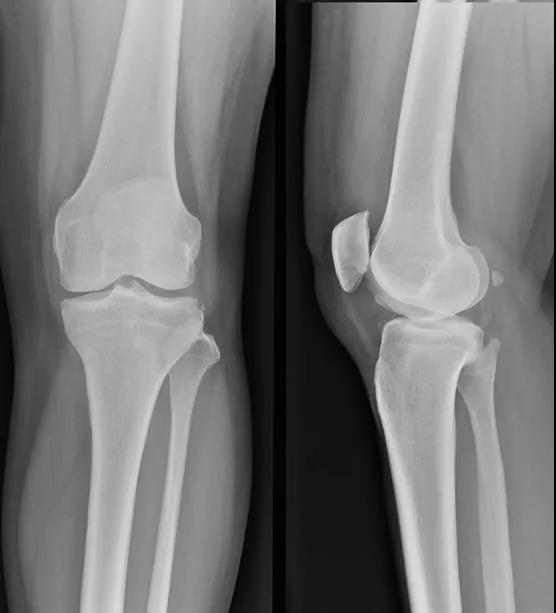

髌骨外上缘穿刺法

定位:髌骨外上缘处与股外侧肌交界处。按压股外侧肌下凹陷处,贴指甲刺入0.5-1cm,有落空感即可。

髌骨外下缘(外侧膝眼)穿刺法

定位:屈膝90°位,髌骨下缘、髌韧带外侧1cm处(外侧膝眼,可看到一小凹陷)。